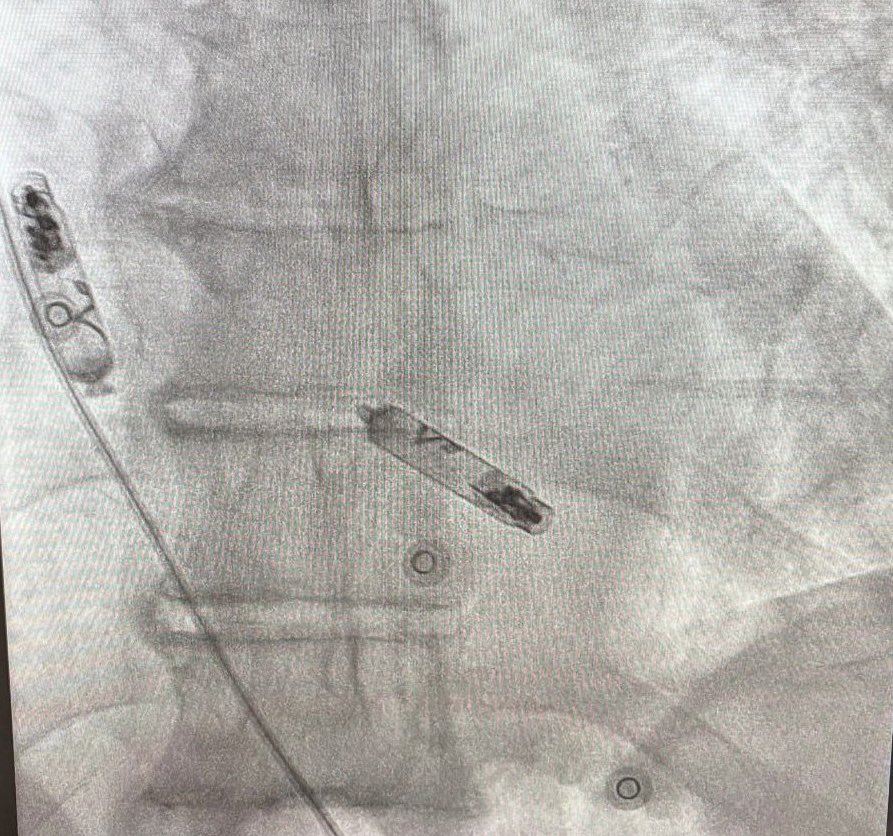

Impact of Left Atrial Posterior Wall Isolation using Pulsed-field Ablation in Patients Undergoing Repeat Catheter Ablation for Atrial Fibrillation #OpenAccess heartrhythmjournal.com/article/S1547-…